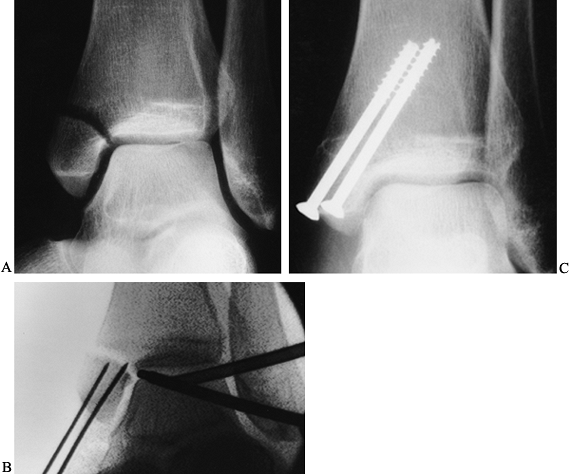

If arthroscopic fracture reduction is

lengths and insert the appropriate size screws (Fig. 93.22A, Fig. 93.22B and Fig. 93.22C).![]() Figure 93.22. Arthroscopically assisted treatment of a medial malleolar fracture. A: Preoperative x-ray study shows a displaced fracture with rotation. B: Figure 93.22. Arthroscopically assisted treatment of a medial malleolar fracture. A: Preoperative x-ray study shows a displaced fracture with rotation. B:

Intraoperative fluoroscopy shows initial fracture reduction and pin

then cross the fracture for screw placement. C: Screw placement and fracture healing 8 weeks postoperative.